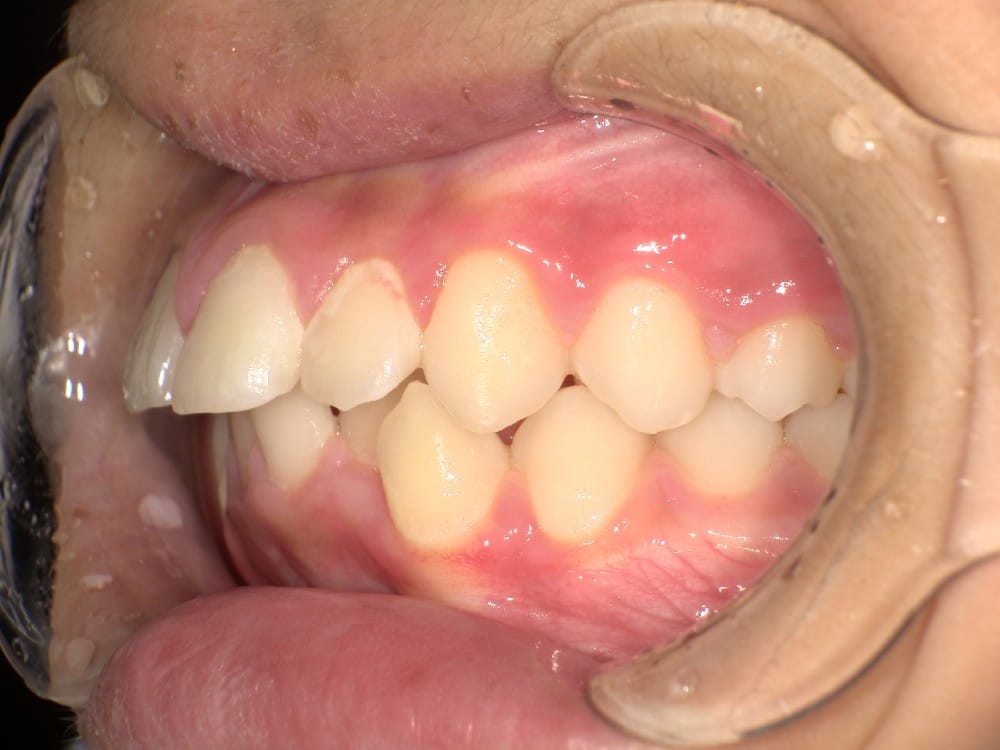

② セファロ(横顔レントゲン)分析

骨格的な問題があるかどうかを数値で評価します。

上顎・下顎の前後関係、前歯の傾斜角度、口元の軟組織のバランスなどを客観的に確認することで、「歯が原因なのか」「骨格が原因なのか」を明確にします。